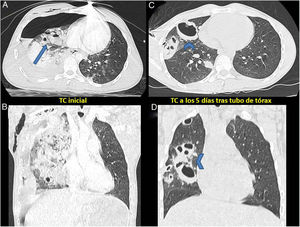

Varón de 17 años que sufre un accidente de moto con traumatismo torácico lateral izquierdo cerrado de alto impacto. No tenía antecedentes de interés. A su ingreso se aprecia en la TC torácica la formación de neumotórax con varias áreas de contusión pulmonar bilaterales (fig. 1 A y B). Se coloca drenaje torácico durante 5 días y, ante la presencia de fuga aérea persistente a esfuerzos máximos, se realiza una nueva TC. En esta, se aprecia expansión casi completa del pulmón y formaciones quísticas de gran tamaño que se corresponden con neumatoceles (fig. 1 C y D).

A y B) TCMD de tórax, corte axial y coronal: extensa hemorragia alveolar derecha en cuyo seno se identifican espacios quísticos con niveles hidroaéreos compatibles con laceraciones pulmonares (flecha). Hidroneumotórax y enfisema subcutáneo derechos. Pequeños focos contusivos pulmonares izquierdos. C y D) TCMD de tórax, corte axial y coronal: reexpansión pulmonar tras tubo de tórax, con práctica resolución de la hemorragia alveolar derecha. Los espacios quísticos hidroaéreos presentes en el estudio previo han perdido los niveles y presentan ahora un aspecto extraño en relación con neumatoceles postraumáticos (puntas de flecha).